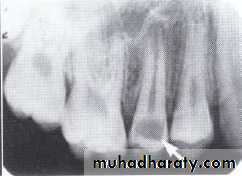

Dentin dysplasia, type I. panoramic & periapical films of the same case show the short and poorly developed roots, obliterated pulp chambers and root canals, and periapical inflammatory lesions.

Dentin dysplasia, type II. panoramic &periapical films of the same case show obliteration of the pulp chamber, reduction in the caliber of root canals, and pulp stones obscuring the flame-shaped pulp chambers.

Periapical inflammatory lesions are associated with some of the mandibular anterior teeth.